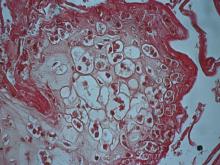

性腫塊病變伴隨膿瘍灶,並形成痂皮。其他內臟無明顯肉眼病變。三、 組織病變: 口唇部皮膚可見表皮棘細胞層增生(圖2)、水腫變性、氣球樣變性;部份表皮細胞角

化過度;表皮層與真皮層之間有紅血球浸潤;表皮層有炎症反應及多數炎症細胞浸潤;

細胞質內可見疑似嗜酸性質內包涵體(圖3)。四、 實驗室檢驗: 1.